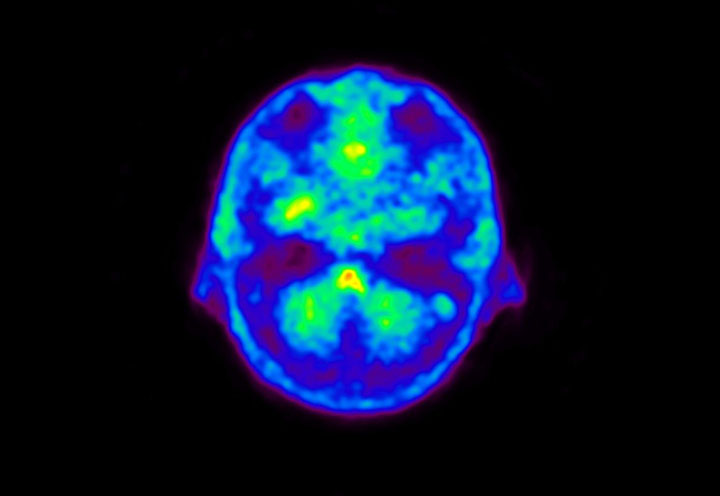

Head / Case5 : Amyloid

Courtesy : Kindai University Hospital

- Imaging protocol

- Injected dose: 4.27 MBq/kg, 18F-Flutemetamol

- Uptake time: 99 minutes

- Scan time: 20 minutes